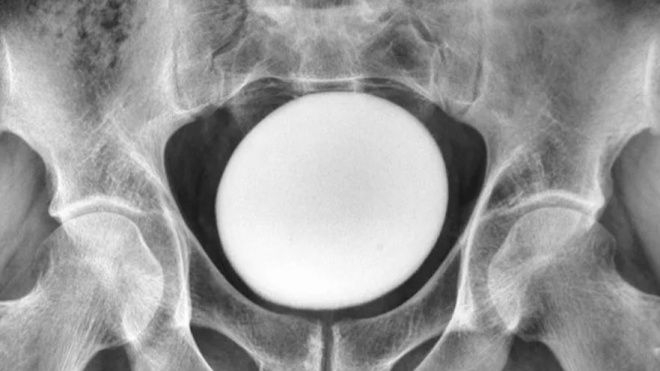

이 덩어리는 골반이나 복벽에 붙어있지 않았다. 초음파 검사 결과 지름 약 11㎝의 달걀 형태의 물체였다.

이란 35세 남성의 방광에서 발견된 타조알 크기의 결석. [라이브사이언스] |

의료진은 이를 비정상적으로 큰 방광 결석으로 진단했다. 결석은 소변 속 미네랄이 결정으로 쌓이면서 자라는데, 약 85%가 칼슘으로 이뤄져 있다.

의사들은 이 결석이 요로를 막거나 압박하지 않는지 확인한 뒤 수술로 제거했다. 꺼낸 결석은 무게 826g, 길이 약 13㎝, 너비 약 10㎝, 높이 약 8㎝였다. 이처럼 수술로 제거해야 하는 거대 결석은 “매우 드물다”고 보고서는 밝혔다.